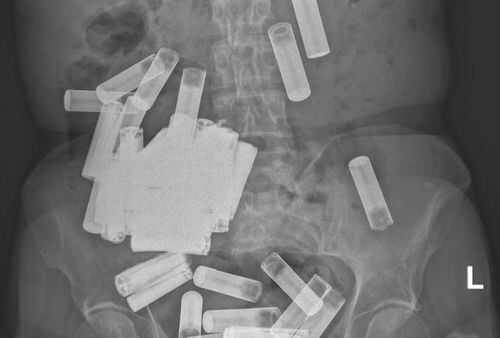

Врачи обнаружили в теле пациентки 55 батареек

После рентгена в теле 66-летней женщины обнаружились многочисленные батарейки АА и ААА — они были как в желудке, так и в кишечнике. Поскольку по счастливой случайности ни один из инородных предметов не препятствовал работе желудочно-кишечного тракта, врачи поначалу решили просто понаблюдать за женщиной, надеясь, что батарейки выйдут естественным образом.

Но в течение недели из тела пациентки вышло всего лишь 5 батареек. Несчастная так страдала от спазмов, что медики приступили к операции и сумели извлечь из тела женщины остальные батарейки. Всего их оказалось 55 штук.